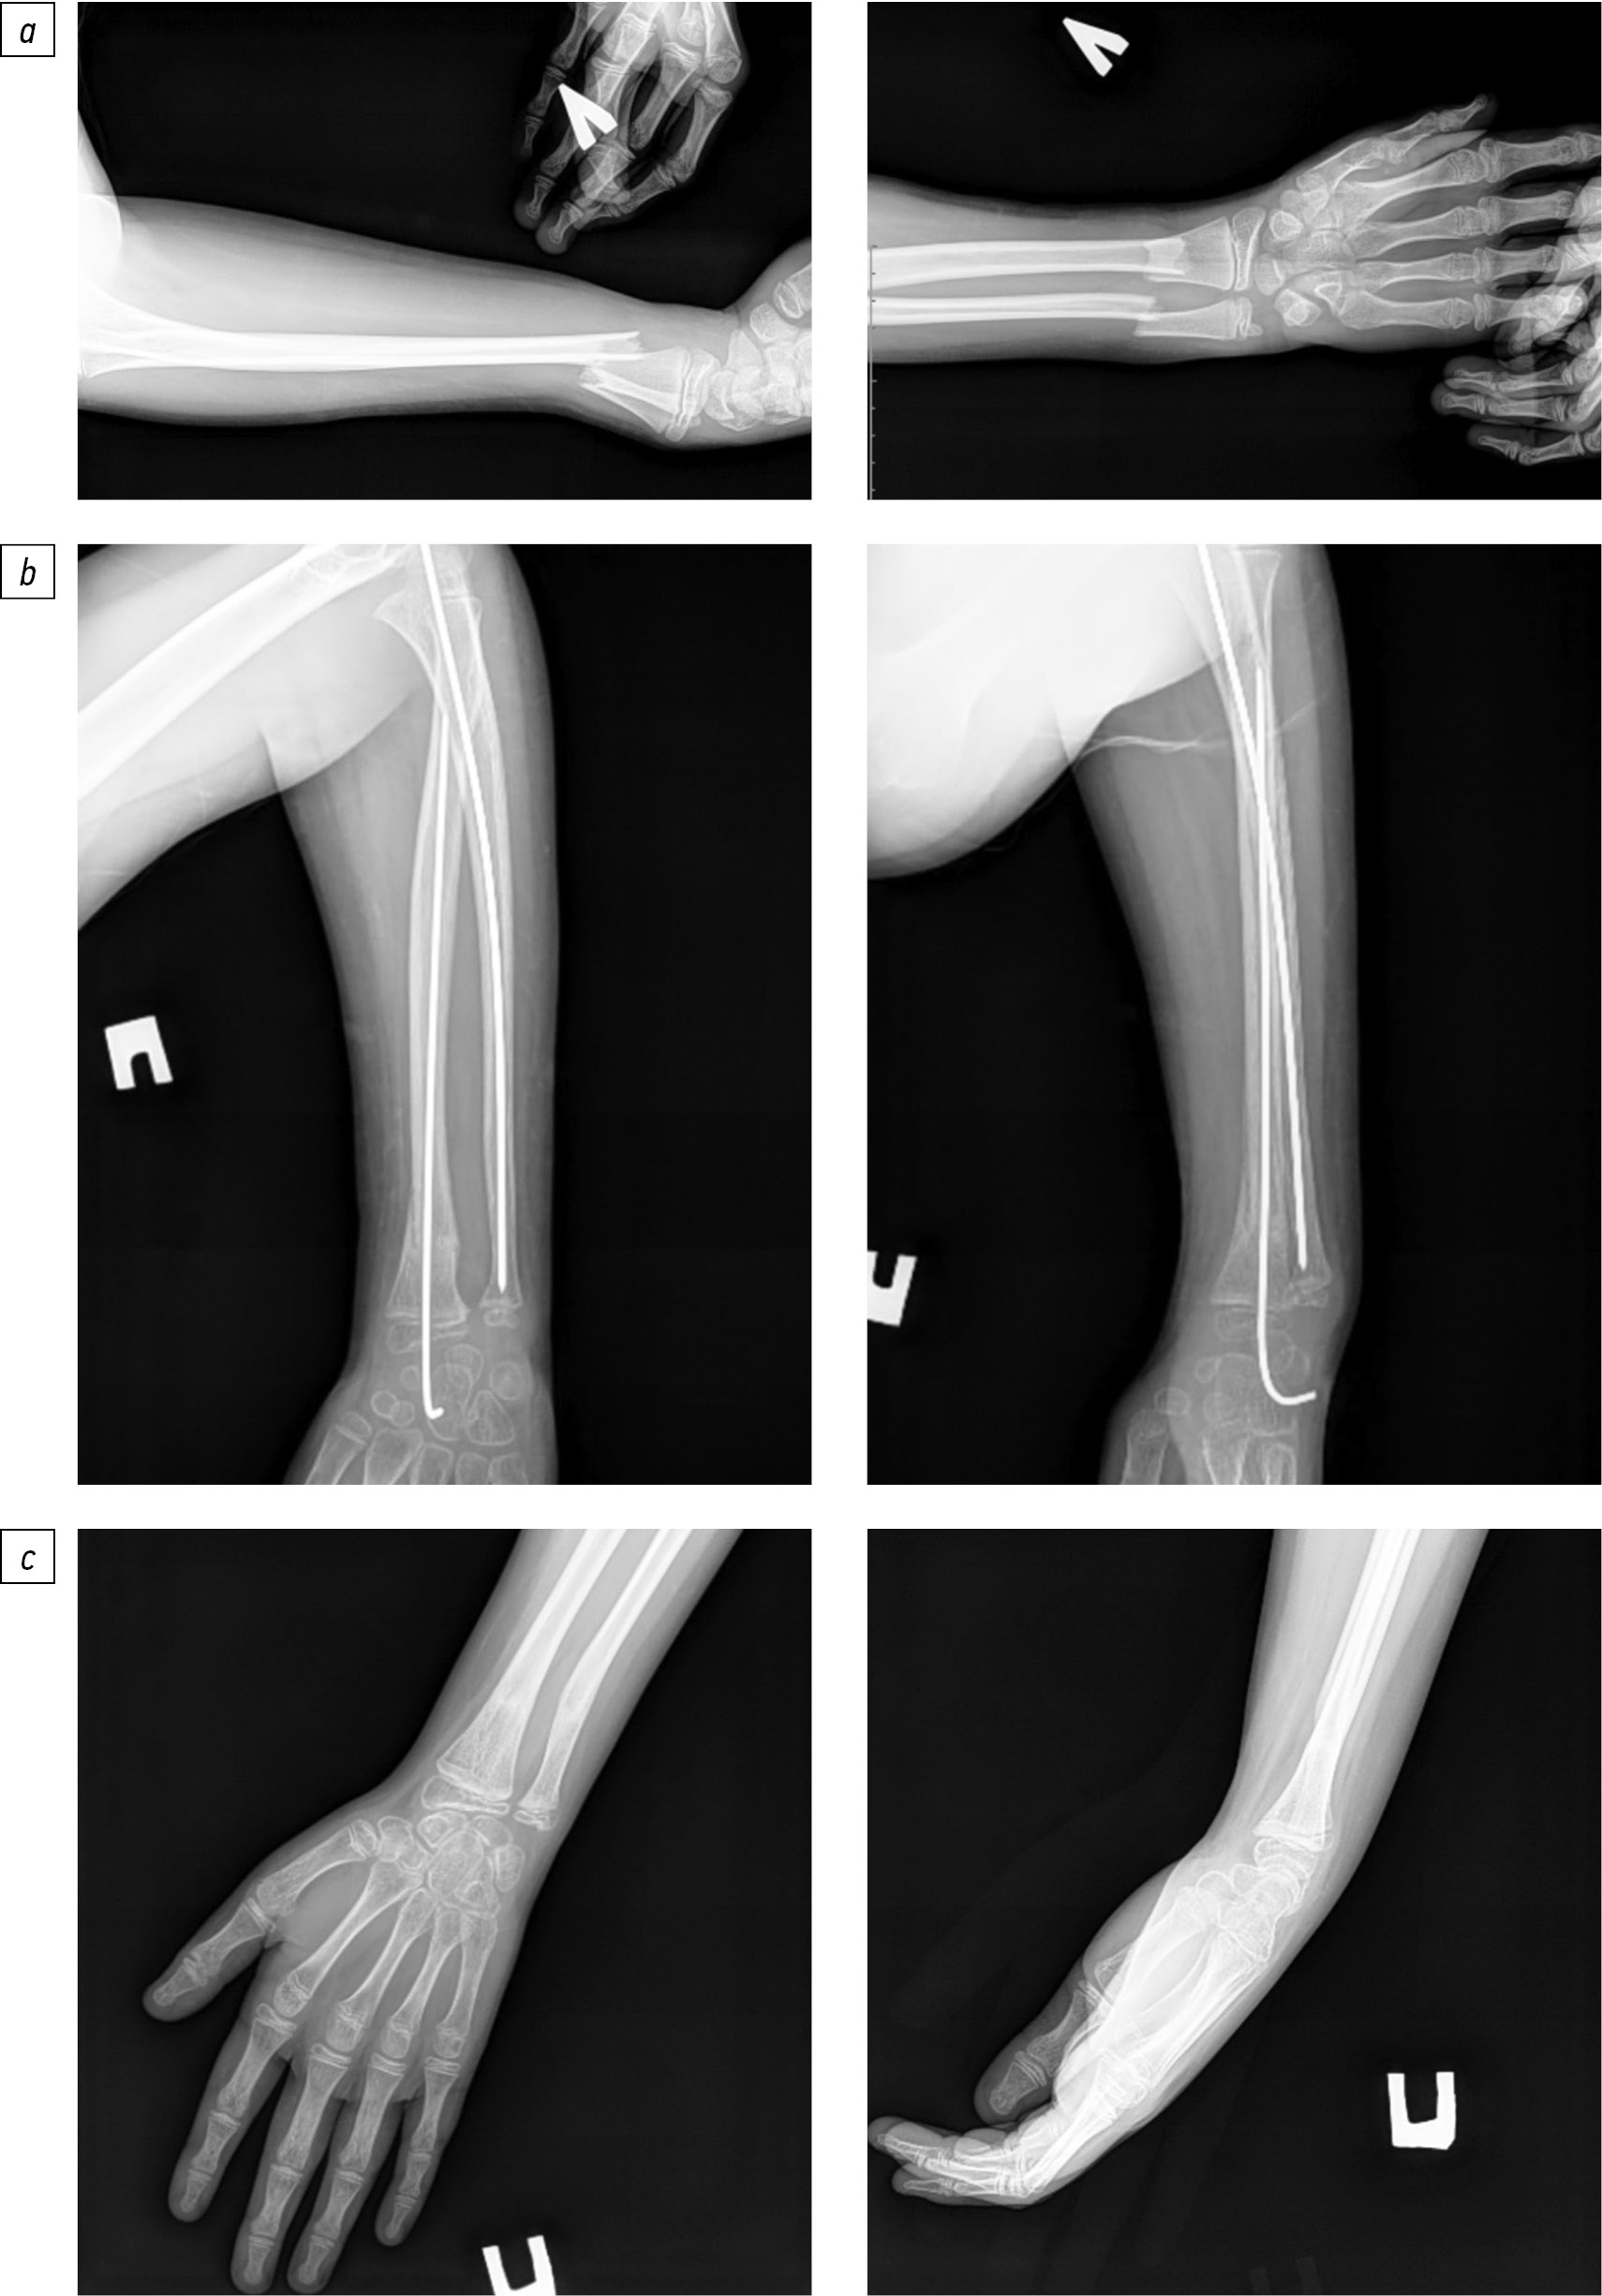

Применение новой методики хирургического лечения не привело к увеличению времени операции по сравнению со стандартной техникой операции (р=0,72). Так, продолжительность оперативного вмешательства по усовершенствованной методике составила 25 (от 20 до 30) мин. При этом способе хирургического лечения по лучевой поверхности предплечья, на расстоянии 2–3 см от проксимального эпифиза лучевой кости, в среднефизиологическом положении, при помощи шила под углом 90° формируют отверстие в костномозговой канал, наклоняя шило по ходу кости. Затем вводят один конец спицы Киршнера и проводят ее в дистальном направлении по костномозговому каналу после выполнения репозиции отломков под контролем С-дуги. Спица, введенная в костномозговой канал, самостоятельно изгибается по ходу введения. Дистальный изогнутый конец спицы упирается в метафиз или эпифиз, обеспечивая стабильность и невозможность смещение отломков. Предварительно конец спицы Киршнера с перьевой двусторонней заточкой дугообразно изгибают на 30° в сторону заточки с целью более безопасного проведения по костномозговому каналу и удобства репозиции. Используют спицы разного диаметра (1,5, 1,8 и 2,0 мм) в зависимости от возраста пациента и ширины костномозгового канала. После введения спицы в зону перелома при сохранении смещения костных отломков возможно ее осевое вращение за свободный конец до достижения анатомической репозиции, производя контроль в режиме скопии на С-дуге (рис. 1 и 2). Спицы Киршнера обеспечивают менее жесткую фиксацию, чем стержни или пластины, однако при правильной установке могут обеспечивать достаточную стабильность для сращения перелома ДОЛК за счет эластичной стабилизации — распор в костномозговом канале (при правильном подборе диаметра спицы и ее изгибе создается контакт с кортикальным слоем, что ограничивает смещение), а также применения гипсовой иммобилизации после оперативного лечения для предотвращения вторичного смещения.

Рис. 1. Рентгенограмма предплечья пациента с нестабильным переломом дистального отдела лучевой кости до оперативного лечения усовершенствованным методом антеградного интрамедуллярного металлостеосинтеза изогнутой спицей Киршнера.

Рис. 2. Рентгенограмма предплечья пациента с нестабильным переломом дистального отдела лучевой кости после оперативного лечения усовершенствованным методом антеградного интрамедуллярного металлостеосинтеза изогнутой спицей Киршнера: а — сразу после лечения; б — в прямой и боковой проекции через 6 мес.

Продолжительность операции по стандартной методике составляла 25 (от 20 до 35) мин и предполагала проведение спицы Киршнера через дистальный отломок лучевой кости. После закрытой репозиции под контролем С-дуги осуществляли фиксацию перелома путем введения спицы через зону перелома в проксимальный костный отломок (рис. 3).

Рис. 3. Рентгенограмма предплечья пациента: a — с сочетанным переломом дистального отдела лучевой кости и локтевой кости в прямой и боковой проекции перед оперативным лечением; b — с нестабильным переломом дистального отдела лучевой кости в прямой и боковой проекции после оперативного лечения традиционным методом ретроградного интрамедуллярного металлостеосинтеза спицей Киршнера; c — с нестабильным переломом дистального отдела лучевой кости в прямой и боковой проекции через 6 мес. после оперативного лечения.